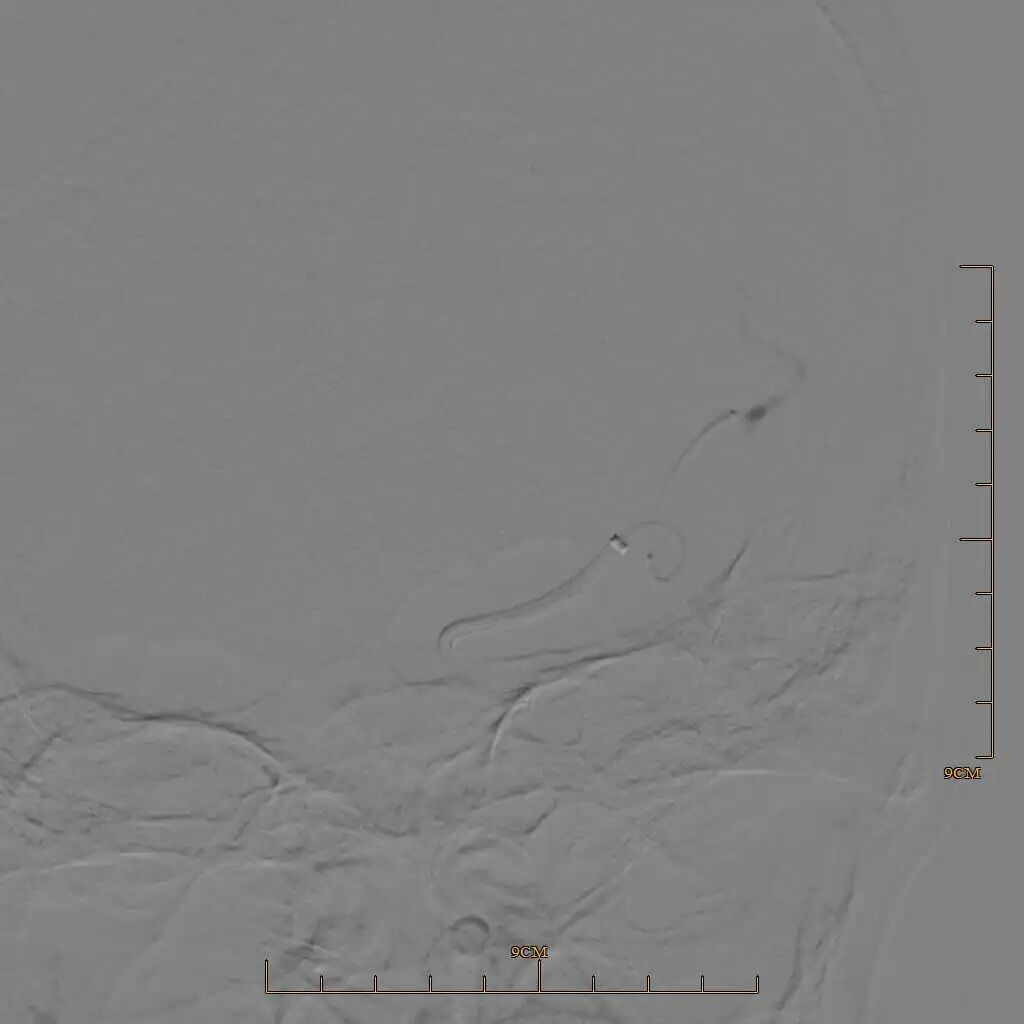

90cm Locaste 088输送导管建立路径,造影提示左侧大脑中动脉M1段闭塞。

动脉长鞘怎么置入有励可说|Locaste 088励楷长鞘及Tarvos微导丝在左侧大脑中动脉闭塞取栓术中的应用_https://www.jmylbn.com_新闻资讯_第8张

动脉长鞘怎么置入有励可说|Locaste 088励楷长鞘及Tarvos微导丝在左侧大脑中动脉闭塞取栓术中的应用_https://www.jmylbn.com_新闻资讯_第9张

动脉长鞘怎么置入有励可说|Locaste 088励楷长鞘及Tarvos微导丝在左侧大脑中动脉闭塞取栓术中的应用_https://www.jmylbn.com_新闻资讯_第10张

Tarvos微导丝携微导管超选大脑中下干M2末端。